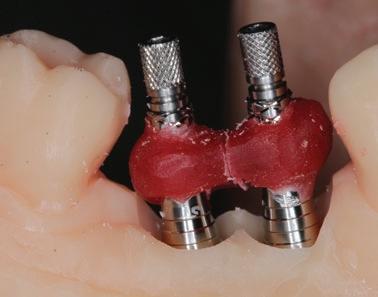

Concepts avancés :

Biomécanique, jumelage, passivité des armatures et concept de la gigue

Occlusion

Profil d’émergence des restaurations

Étapes de mise en bouche de la restauration